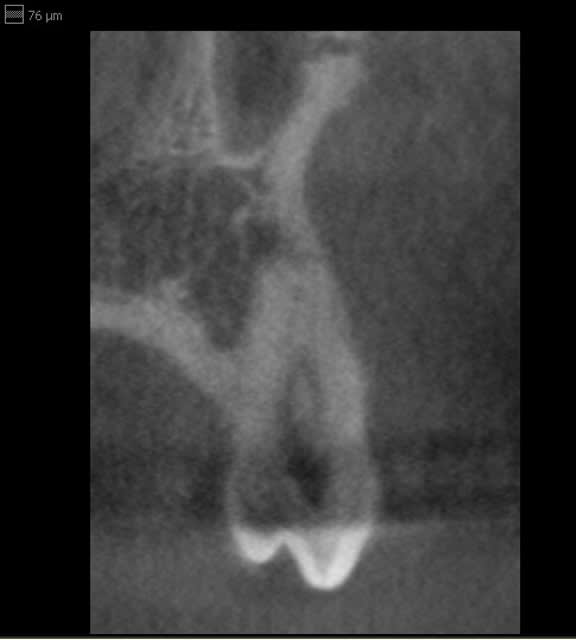

Il ya encore un souci d'artéfact important quand il y a un fort contraste exemple obturation endo très dense ou tenon métallique ((flèche sur image jointe).

Juste le temps de faire une capture...